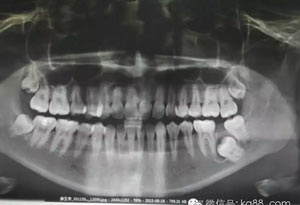

圖20.術(shù)后全景片檢查:37缺損接近下頜骨邊緣。特別提示用挺的力量、防止下頜骨骨折。

20.jpg